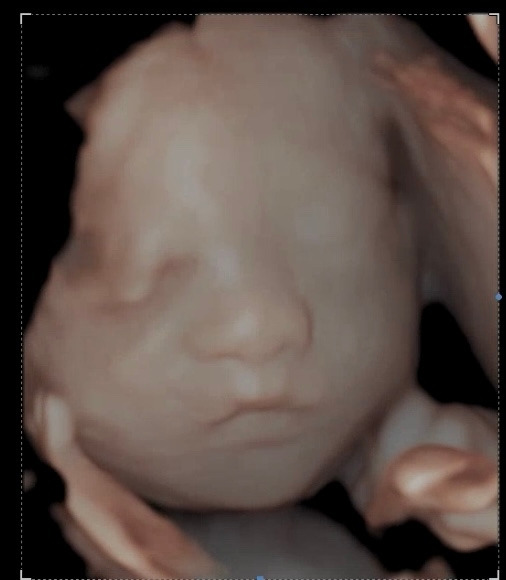

그렇게 치즈는 나날이 불안했던 나를 안심시켜주듯 잘 자라주고 있었다. 1차 입체초음파를 하고 나니 성별이 궁금해졌다. 물론 우리에게 아기의 성별은 중요하지 않았다. 아들이든 딸이든 감사한 마음 뿐이었으니... 단지 미리 아기의 옷이나 소품을 준비하고 싶은데 어떤 색으로 준비하면 좋을지 망설여지는 순간들이 있었기 때문. 그냥 단순한 궁금증이었다. (사실 그 또한 중립적인 색으로 준비하면 될 일이기도 하다.) 그러나 병원에 따라 성별을 알려주지 않는 곳도 있다고 하고, 알려주는 곳이 있다 하더라도 느즈막하게 알려준다고 하기에 우리는 성별을 감식할 수 있는 편법을 검색해봤다.

KakaoTalk_20231220_233651190.jpg 2차 입체 초음파